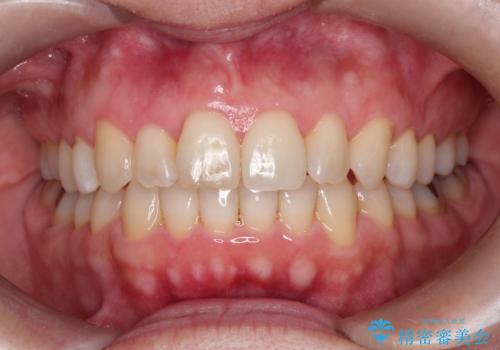

【インビザライン 】前歯のガタガタを治したい

- 前歯のガタガタを主訴に来院されました。

インビザライン で治療しました。途中は使用時間が20時間を切ることもありましたが、それでも頑張って使っていただき1年半で矯正終了することができました。